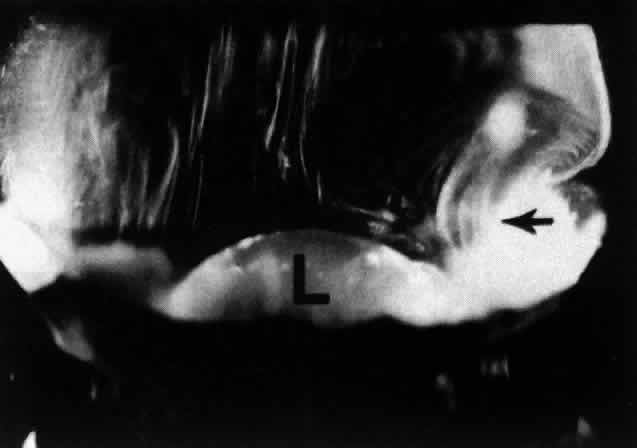

The vitreous base is a three-dimensional zone. It extends 1.5 to 2 mm anterior to the ora serrata, 1 to 3 mm posterior to the ora serrata,48 and several millimeters into the corpus vitreous itself.98 The vitreous base is virtually inseparable from the peripheral retina. Thus, dissection of retina off the vitreous cortex in autopsy eyes always results in a band of retina that remains attached to the peripheral vitreous at the vitreous base (see Fig. 2). Similarly, clean dissection of the vitreous base and peripheral vitreous cortex from the retina during vitrectomy surgery is extremely difficult to achieve. The ultrastructural correlate of this surgical observation may relate to vitreous fiber insertions at the vitreous base where they “splay out” (see Fig. 6) to insert anterior and posterior to the ora serrata (see Fig. 4H). The anteriormost fibers form the “anterior loop” of the vitreous base (Fig. 11), a structure that is important in the pathogenesis and surgery of anterior PVR. In the posterior portion of the vitreous base, vitreous fibers are closer together than elsewhere. Gartner99 has found that in humans the diameters of collagen fibrils in the vitreous base range from 10.8 to 12.4 nm, with a major period of cross striations of 50 to 54 nm. Hogan48 demonstrated that just posterior to the ora serrata, heavy bundles of vitreous fibrils attach to the basal laminae of retinal glial cells. Studies by Gloor and Daicker100 showed that cords of vitreous collagen insert into gaps between the neuroglia of the peripheral retina. They likened this structure to Velcro and proposed that this would explain the strong vitreoretinal adhesion at this site. In the anterior vitreous base, fibrils interdigitate with a reticular complex of fibrillar basement membrane material between the crevices of the nonpigmented ciliary epithelium.101 The vitreous base also contains intact cells that are fibroblast-like anterior to the ora serrata and macrophage-like posteriorly.101 Damaged cells in different stages of involution and fragments of basal laminae, presumed to be remnants of the embryonic hyaloid vascular system (vasa hyaloidea propria) that filled the primary vitreous, are also present in the vitreous base.101

Fig. 11. Morphology of anterior loop in human vitreous base. Central and peripheral vitreous structure in a 76-year-old man. The posterior aspect of the lens (L) is seen below. Fibers course anteroposteriorly in the central vitreous and insert at the vitreous base. The “anterior loop” configuration at the vitreous base is seen on the right side of the specimen (arrow). (Sebag J: The Vitreous--Structure, Function and Pathobiology. New York, Springer-Verlag, 1989)